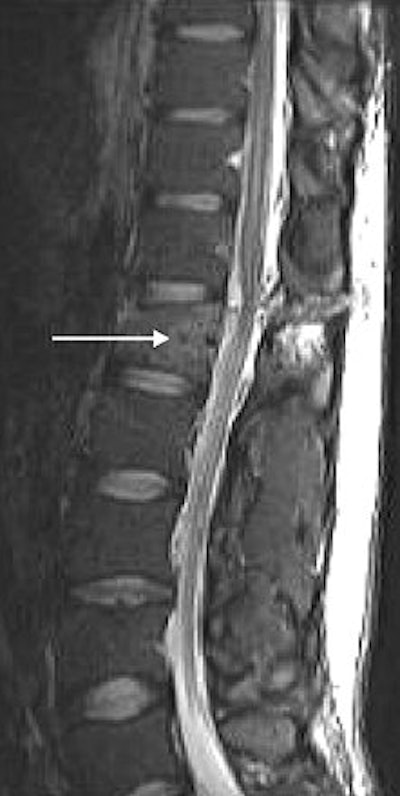

| Inversion-recovery sagittal MR images of lumbar spine in 31-year-old man. Chance fracture of L1 shows marked high signal in interspinous ligaments and soft tissues (arrowheads). Bone marrow edema (arrows) is seen in pedicle and vertebral body. |

MR showed marked soft-tissue damage through the posterior elements and surrounding soft tissues in all patients. "MRI evaluation provides information regarding the integrity of the posterior and middle-column ligaments, annulus fibrosis, and spinal cord in neurologically injured patients," they added.